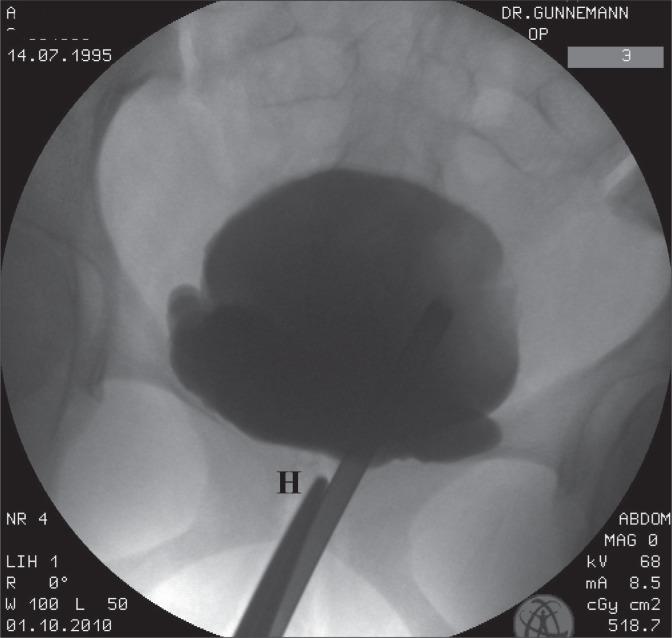

We applied unilateral midurethral pressure during a radiological investigation of a 15-year-old female patient who had undergone 2 surgeries for ureteric reflux.

On injection of the dye into the bladder, reflux was noted in the left ureter, and this disappeared within 2-3 seconds after pressure was applied on 2 successive occasions in the midurethral area of the vagina.